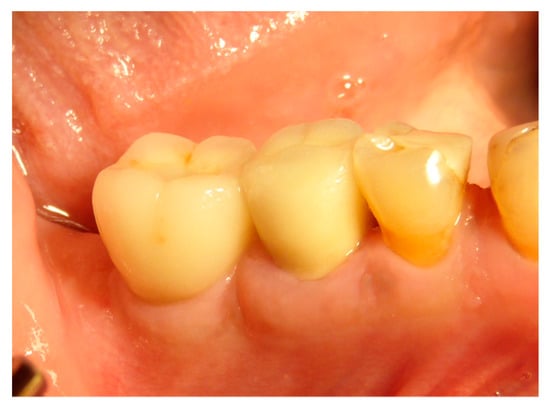

The faraway graft procedure follow up is 40 months and the near graft procedure follow up is 9 months (Average 24.5 months). The faraway implant follow up is 35 months and the near implant follow up is five months. The success rate of the tooth graft procedure is 99.1% (one site was infected and lost the regeneration and the implant) (Figure 6, Figure 7 and Figure 8). In all cases, after the all implants were inserted, complete osseointegration after proper healing period was achieved. After the healing period, hard and soft tissues were stable (Figure 9, Figure 10 and Figure 11). The healing of soft tissues after grafting procedures was particularly free of complications. The implant success rate was 98.94% (one implant failed).

Figure 7. Dental element 46 to be extracted with the need for ridge maintenance due to an extensive interradicular defect.

Figure 8. Ridge maintenance through the use of the extracted element and cover with a resorbable membrane.